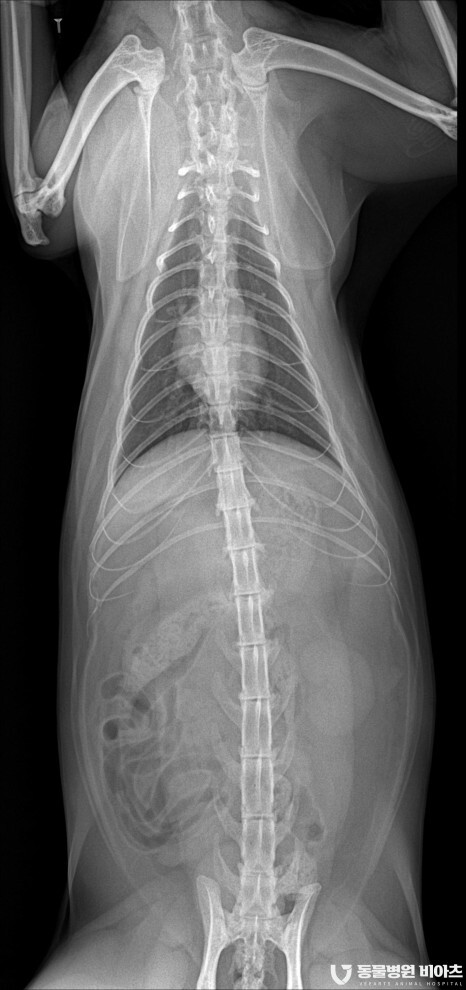

엑스레이 촬영

흉부 엑스레이와 발톱 부위의 엑스레이 촬영을 합니다.

마취 전 검사와 병변 부위의 검사입니다.

병변 부위를 제외하고는 특이 소견이 없었습니다.